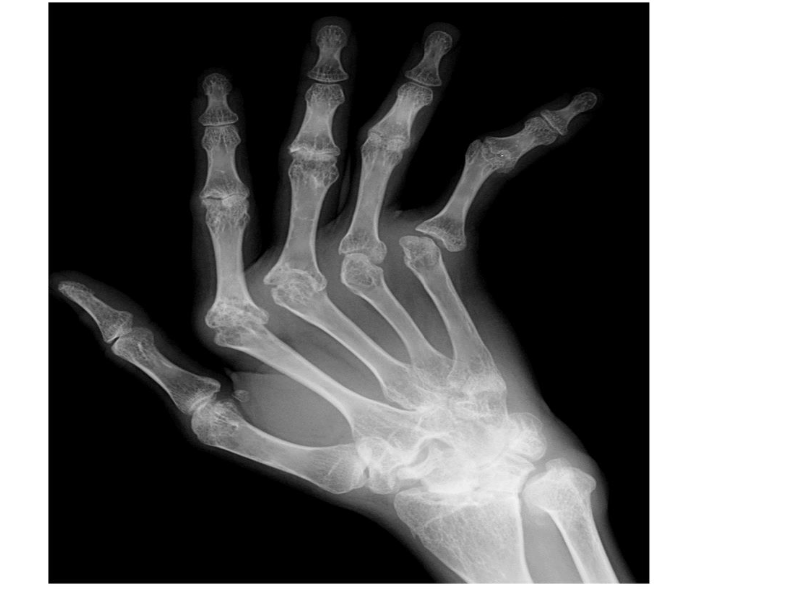

Identify the structures ? view? what joint ?

Wrist joint -AP

Scaphoid

Lunate

Triquetrum

Pisiform

Trapezium

Trapezoid

Capitate

Hamate